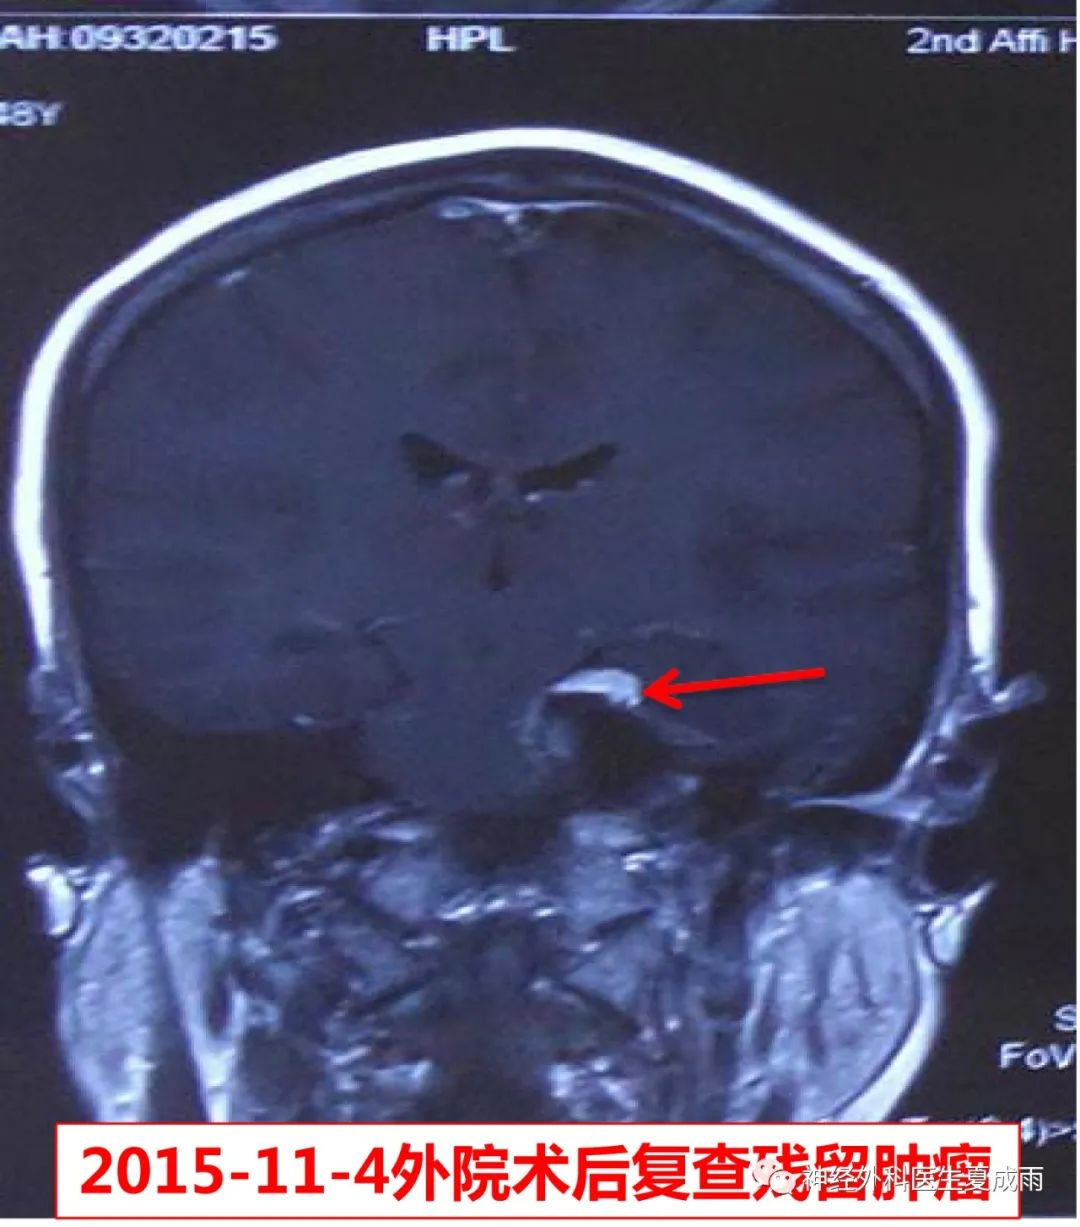

因“左岩斜区脑膜瘤术后3年余,左面部麻木加重3月”于2019-2-7入院。既往患者于2015年11月曾在邻省某医院行乙状窦后入路肿瘤切除手术。

外院手术前后磁共振对比,见海绵窦残余少许肿瘤。